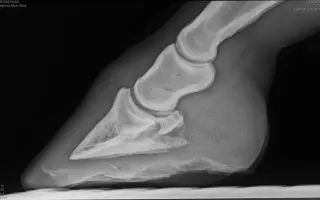

Urobili sa kontrolné RTG a testy zápalu z krvi. Moly mala najvyšší merateľný zápal v krvi a podľa rtg sa jej absces / nekróza tkanív vrátila po vysadení ATB, dostalo sa to do burzy a synovialnych tkanív – veľmi zlá prognóza. Po niekoľko hodinovej konzultácii a zvažovaní možnosti ktoré boli len 2:

Po pár dňoch v novom domove u nás však náhle začala silno krívať. Spočiatku sa zdalo, že ide o bežný absces v kopyte, no napriek liečbe sa jej stav nelepšil. Po viacerých vyšetreniach a konzultáciách sme ju museli previezť na kliniku do Ostravy, kde jej bol chirurgicky vyrezaný hlboký absces v kopyte. Momentálne je hospitalizovaná a čaká ju ďalšia liečba a rekonvalescencia.